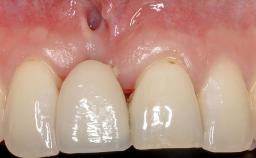

It is sometimes necessary to remove and replace compromised implants. This case is a clear example of the need for multiple steps to achieve an optimal therapeutic result for patients with non-salvageable implants. It illustrates how the lost soft and hard tissues were rebuilt in a sequence that improved the healing of the hard tissues and assured their long-term stability. The 35-year-old healthy patient presented with clinical attachment loss on the proximal and lingual surfaces of the natural dentition. Some gingival recession was present on natural teeth, particularly in the posterior sextants (S1, S3, S4, and S6).